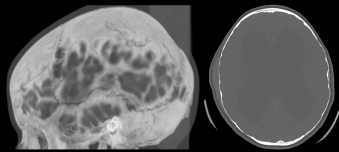

- l’imagerie, qui montre :

- la cause de l’HTIC

- ses complications (engagement, Chiari, hydrocéphalie)

- ses conséquences osseuses (ci-contre) :

- empreintes digitiformes

- sutures étirées, disjointes

- voûte amincie voire lacunaire

- platybasie, selle turcique vide